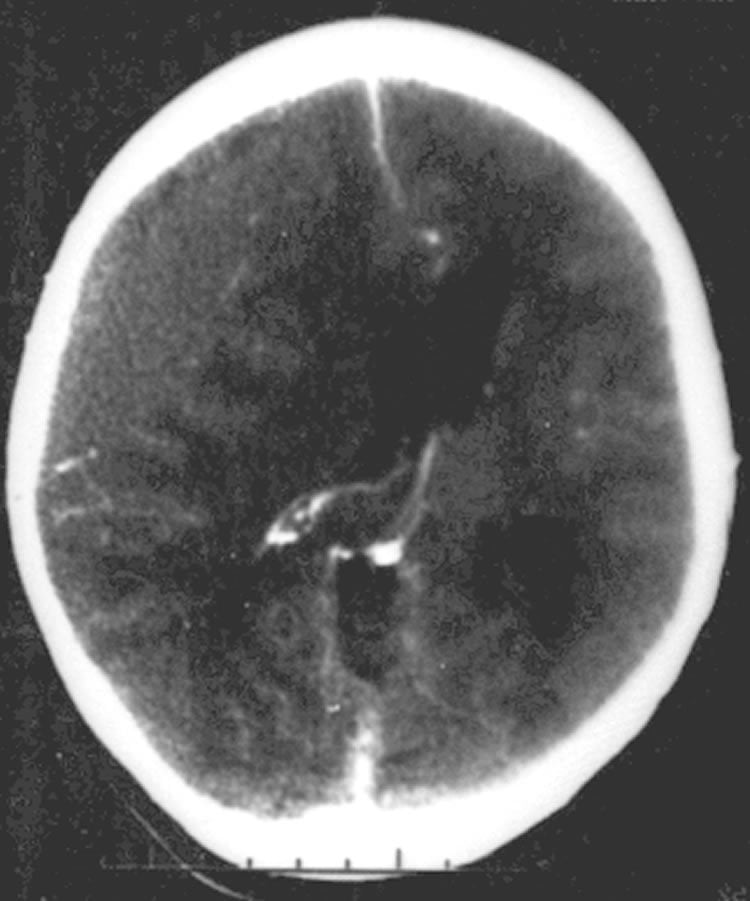

Image Source: The image is credited to Jfdwolff and is licensed Creative Commons Attribution-Share Alike 3.0 Unported